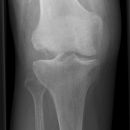

Kniegelenk

Tibiakopf